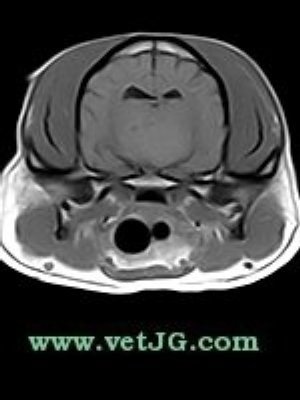

RESONANCIA MAGNÉTICA

TC

AXIAL